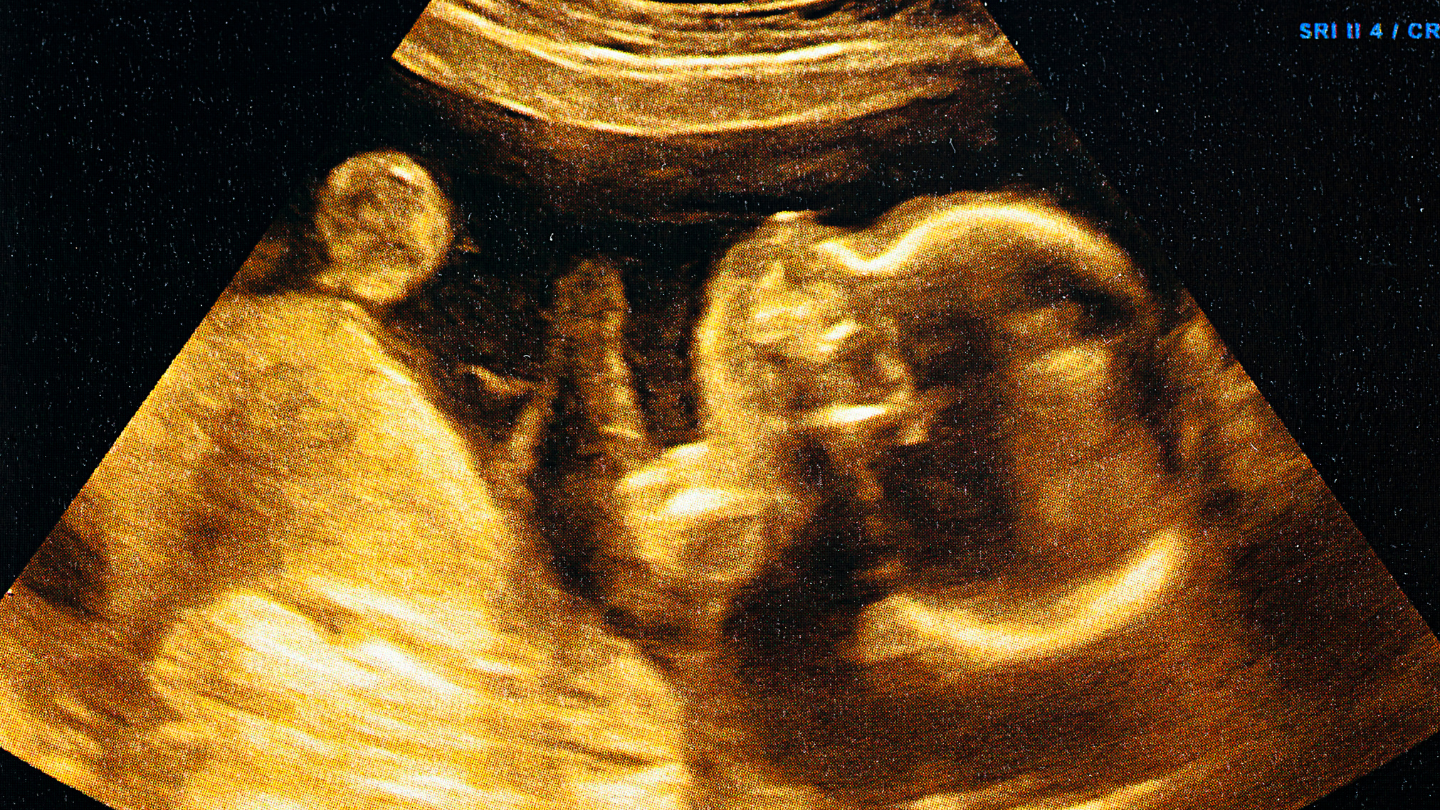

Hình ảnh thai nhi 37 tuần trong bụng mẹ

Nếu quan sát hình ảnh thai 37 tuần trong bụng mẹ qua siêu âm, mẹ sẽ thấy:

- Bé cuộn tròn trong tư thế đầu quay xuống.

- Không gian trong tử cung đã khá chật.

- Thai nhi ít xoay trở hơn so với các tuần trước.